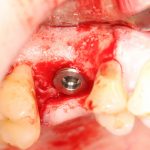

Простой синуслифтинг. Часть I.